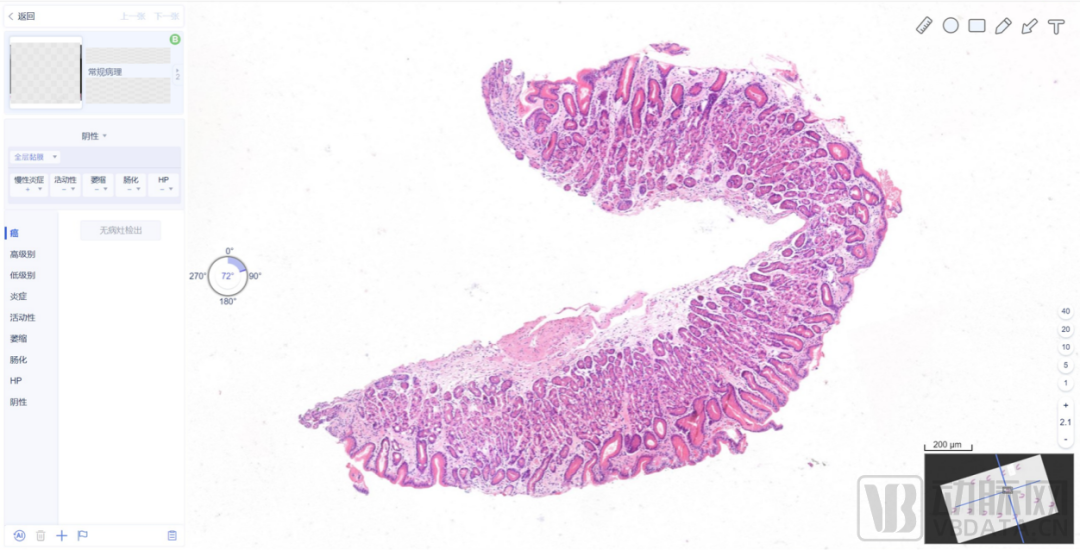

数字化病理科建设模块介绍

数字化建设模块图

来源:蛋壳研究院